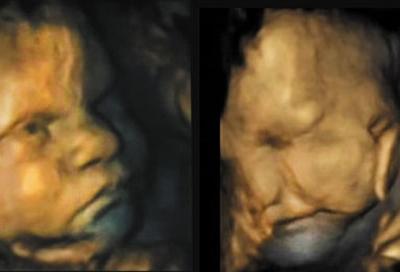

研究指婴儿在出生前16周已会做表情

研究指婴儿在出生前16周已会做表情 (神秘的地球)据香港媒体报道,英国达勒姆大...